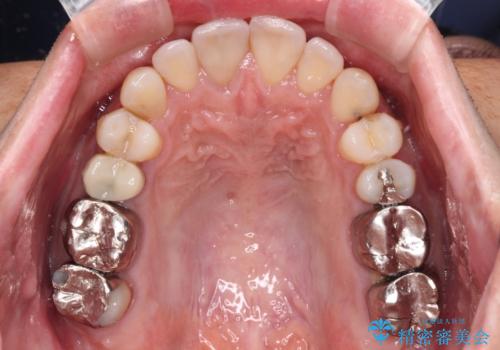

受け口傾向の咬み合わせ 前歯のデコボコをワイヤー矯正で素早く改善

この患者様もクロスバイトはあっという間に改善され、1年強で速やかに治療を終えることができました。